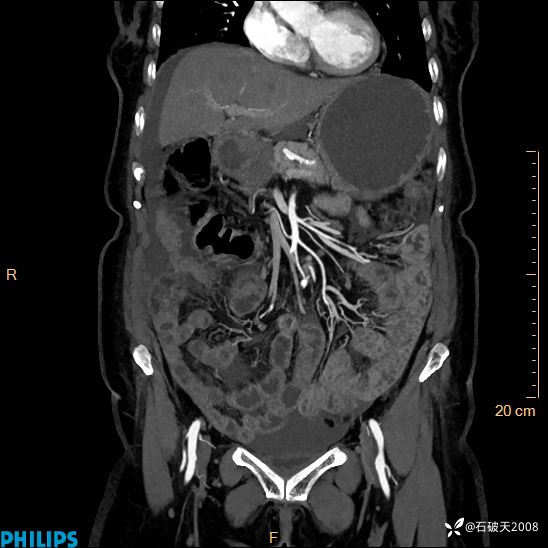

动脉期